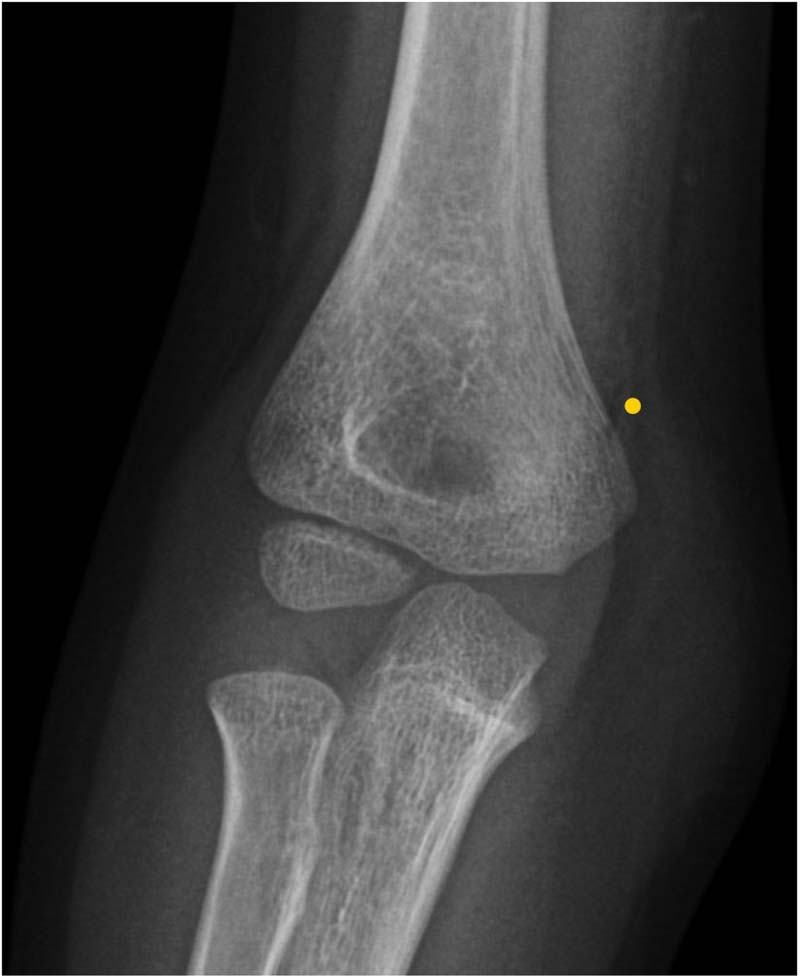

在过去两年中,患儿发生了三次上肢骨折:右侧(图1)和左侧(图2)肱骨髁上骨折,以及右侧肱骨内侧髁骨折(图3)。所有骨折均由家中或学校发生的轻度至中度外力创伤所致,且均与体育运动无关。骨折在经过4-5周的石膏固定后愈合,无后遗症。无骨痛、腹痛、排尿或排便习惯改变或其他全身性症状,也无提示儿童虐待的体征。

图3